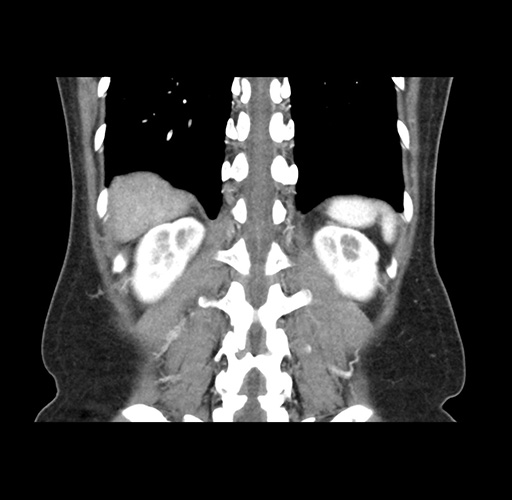

Imaging Analysis

Look through the patient's CT scan to identify any areas of concern for the necessary procedure.

Based on your CT findings, which issue(s) would give reason for "planned slowing down moment(s)" in this case?